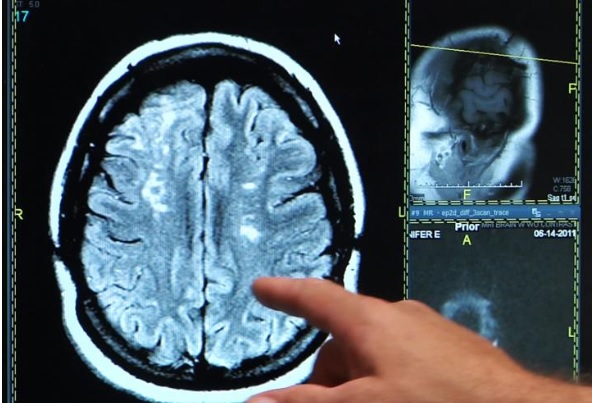

L'AVC est la cause la plus fréquente d'incapacité chez les adultes. Le parcours typique de récupération implique une thérapie de réadaptation intensive. Au cours des premières semaines suivant un AVC, les patients ressentent des améliorations au fur et à mesure que le cerveau se reconfigure, mais finissent par atteindre un maximum et retrouvent rarement leurs capacités de départ.

En injectant un médicament appelé chondroïtinase ABC (ChABC) dans la moelle épinière de rats, modèle d’AVC, 28 jours après l’événement, les chercheurs constatent un « recâblage amplifié des circuits reliant le cerveau à la moelle épinière » et ainsi une amélioration de la récupération. Cette thérapie « vertébrale » et innovante, combinée à une thérapie classique de réadaptation, amplifie encore la récupération. « C’est une preuve tangible qu'il existe des options supplémentaires pour les patients victimes d’AVC et atteints de handicap physique permanent (comme une paralysie ou des troubles moteurs). « Il y a donc un espoir de réduire ces déficits et de rétablir au mieux la qualité de vie, même des années après l'AVC », commente l’auteur principal, Ian Winship, professeur agrégé de psychiatrie.

Des déficits impossibles à traiter ? C’est ce que l’on croyait et on demandait aux patients de vivre avec…Mais ici, l'injection de ChABC dans la moelle épinière ouvre un nouvel espoir. Le médicament agit sur les composants qui entourent les cellules du système nerveux et libère la croissance de nouvelles connexions en permettant de nouvelles connexions entre les zones motrices non affectées dans le cerveau et les réseaux spinaux qui contrôlent le mouvement. Ainsi, l'injection de ChABC un mois après AVC et sans réadaptation permet déjà des améliorations modérées des déficits sensorimoteurs. Mais en combinant la thérapie vertébrale et la thérapie de réadaptation, les sujets se rétablissent mieux et sont capables d'effectuer à nouveau certaines tâches sensorimotrices.